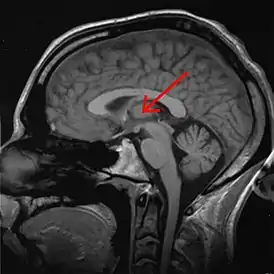

Тала́мус, иногда — зри́тельные бугры (лат. thalamus; от др.-греч. θάλαμος «комната, камера, отсек») — отдел головного мозга, представляющий собой большую массу серого вещества, расположенную в верхней части таламической области промежуточного мозга хордовых животных, в том числе и человека. Впервые описан древнеримским врачом и анатомом Галеном. Таламус — это парная структура, состоящая из двух половинок, симметричных относительно межполушарной плоскости. Таламус находится глубже структур большого мозга, в частности коры или плаща. Под таламусом расположены структуры среднего мозга. Срединная (медиальная) поверхность обеих половинок таламуса одновременно является верхней боковой стенкой третьего желудочка головного мозга[2][3][4].

![]() Таламус человека на МРТ-снимке, отмечен стрелкой | |